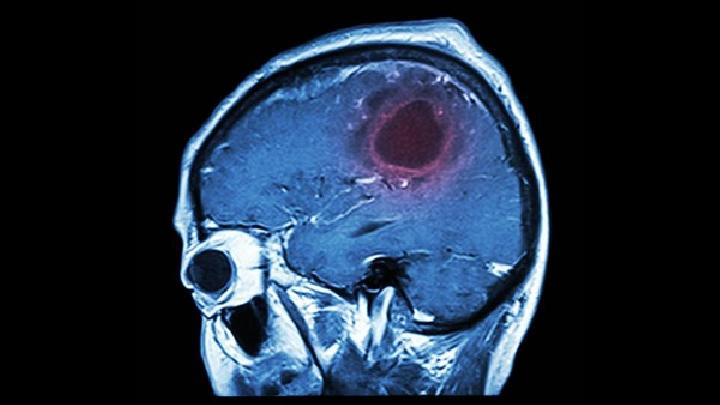

隐球菌性

脑膜炎

可以分为亚急性脑膜炎和亚急性脑膜炎,是由新型隐球菌的

隐球菌性脑膜炎是由于新型隐球菌感染到脑实质和脑膜所引起的,这种病的症状不典型和不规范的治疗使这种病的病死率很高。这种病的主要传染源是鸽新型隐球菌,隐球菌在我们的脑内大量繁殖而且产生大量的毒性因子,从而引起隐球菌性脑膜炎。